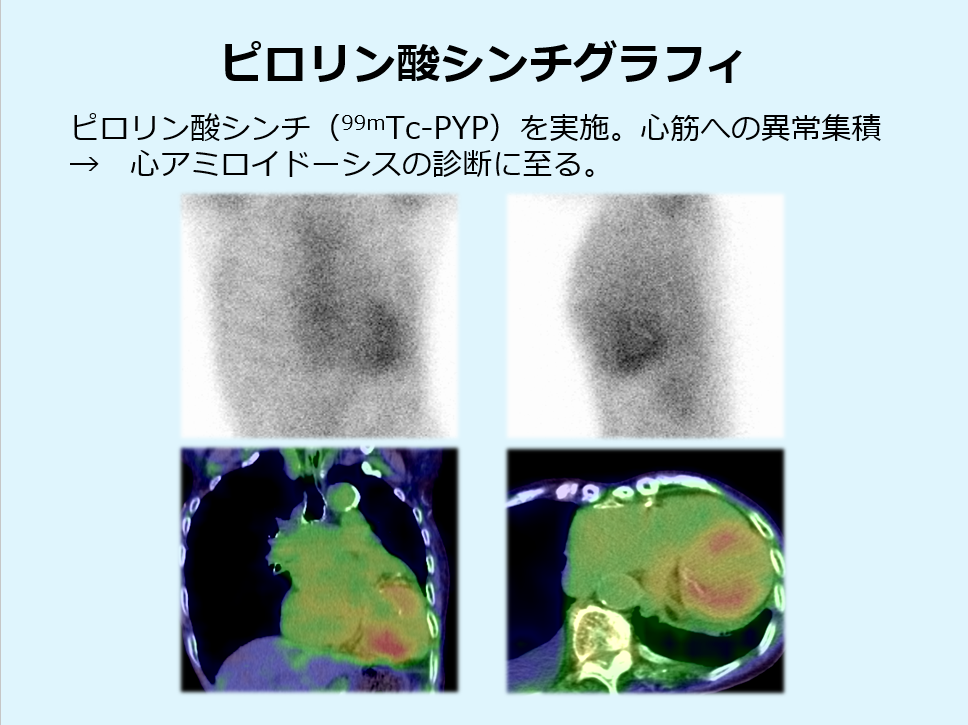

心アミロイドーシスを疑い、ゴールドスタンダードとされているピロリン酸シンチを実施し、心筋に異常な集積を認め、トランスサイレチン型心アミロイドーシス診断となりました。

(ガイドライン上、ピロリン酸シンチ陽性では心筋生検を割愛してよい。)